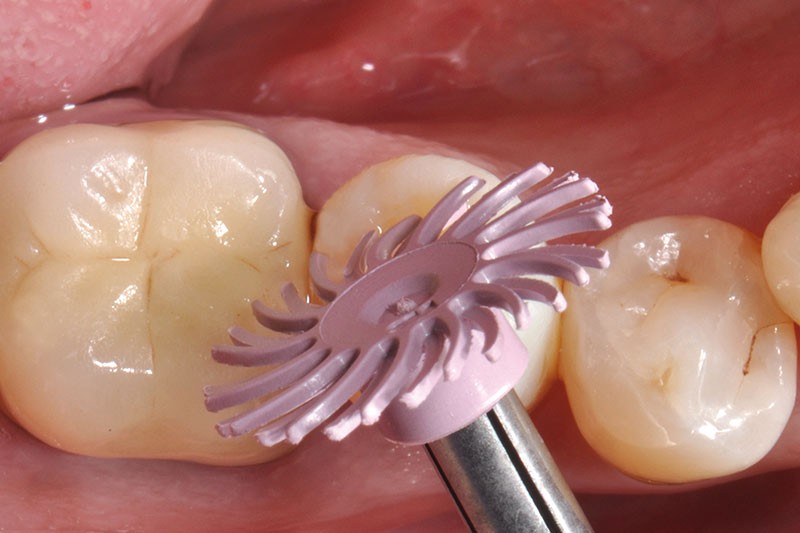

27, 28, 29. La couronne transitoire est pré-polie avec la roue spirale 3M™ Sof-lex™ beige puis polie avec la roue spirale diamantée 3M™ Sof-lex™ rose.